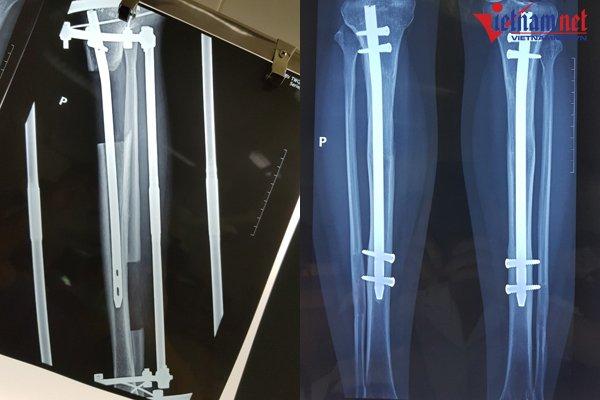

Tuy nhiên từ năm 2010 đến nay, BV 108 cải tiến kĩ thuật, đặt chiếc đinh dài trong ống tủy xương trước khi cắt, giảm số đinh xuyên qua xương chỉ còn 4 đinh và thời gian nằm tại giường chỉ còn 2-3 tháng. Nhờ có đinh cố định, xương khi liền sẽ không bị chệch.

Để đặt đinh, bác sĩ sẽ rạch da dài khoảng 1,5-2 cm dọc mặt trước gân bánh chè, sau đó khoan ống tủy và đóng một đinh dài 24-28cm vào ống tủy xương chày.

Sau khi đóng đinh vào xương chày, vòng cung phía trên liên kết với 2 đinh Kirschner 2 mm được xuyên chéo nhau ở phần sau của đầu trên xương chày, cách khe khớp gối 2 cm, trên đầu đinh nội tủy khoảng 2 - 3mm.

Vòng cung phía dưới liên kết với 2 đinh Kirschner đường kính 2 mm được xuyên chéo nhau ở đầu dưới xương chày phía trên khe khớp 2cm và nằm phía dưới đinh nội tủy. Các đinh Kirschner được căng bằng dụng cụ căng đinh.

Hai vòng khung trên và dưới được liên kết với nhau bằng 3 thanh liên kết có ren ngược chiều, điều chỉnh độ dãn của xương.

Khi đạt đến chiều cao mong muốn, bác sĩ sẽ bắt chốt 2 đinh lại với nhau và tháo bỏ khung ngoài. Bệnh nhân sẽ được bó bột, sau đó bắt đầu tập đi dưới sự trợ giúp của khung hoặc nạng.